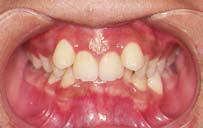

阻礙清潔 滋生細菌

牙齒參差不齊、爆牙、哨牙、牙縫過大、牙齒倒及、咬合過深都為常見需要接受矯齒的情況。學會會長梁訓成醫生指出,「牙齒參差不齊,除了影響外觀,亦會容易積藏食物殘渣;爆牙會阻礙牙齒清潔,令牙垢積聚,容易滋生細菌從而形成牙菌膜,更會增加蛀牙及牙周病的風險;牙齒倒及和咬合不正皆會影響進食和發音,更可能令牙齒過度磨蝕;牙縫過大會容易在說話時濺出口沫,影響社交。因此,矯齒治療不但能美化儀容及提升個人自信,更能改善牙齒咬合排列,有助牙齒及牙肉健康,並改善發音及咀嚼能力。」

■牙齒不齊除會影響外觀,亦會阻礙清潔,容易滋生細菌,長遠影響口腔健康。